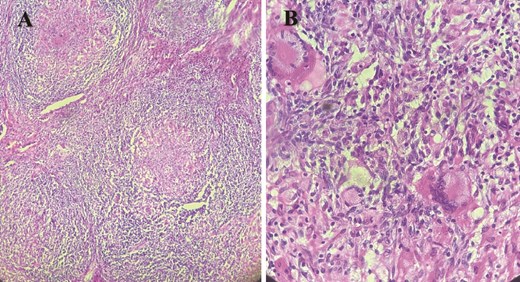

Macroscopique examination of the speciman schowed revealed inflammatory granulomatous epithelio-giganto-cellular changes with caseous necrosis, suggestive of tuberculosis (Fig. 3).

Histological images showing granulomatous inflammatory changes with epithelioid giant cells, as well as early caseous necrosis.

However, it is the histopathological examination that confirms the diagnosis of tuberculosis by revealing epithelioid and gigantocellular granulomas associated with caseous necrosis. These granulomas are present in our patient but their frequency varies according to other studies; N. Bel Kahla et al. found ⁓27% of cases in their case series [10].